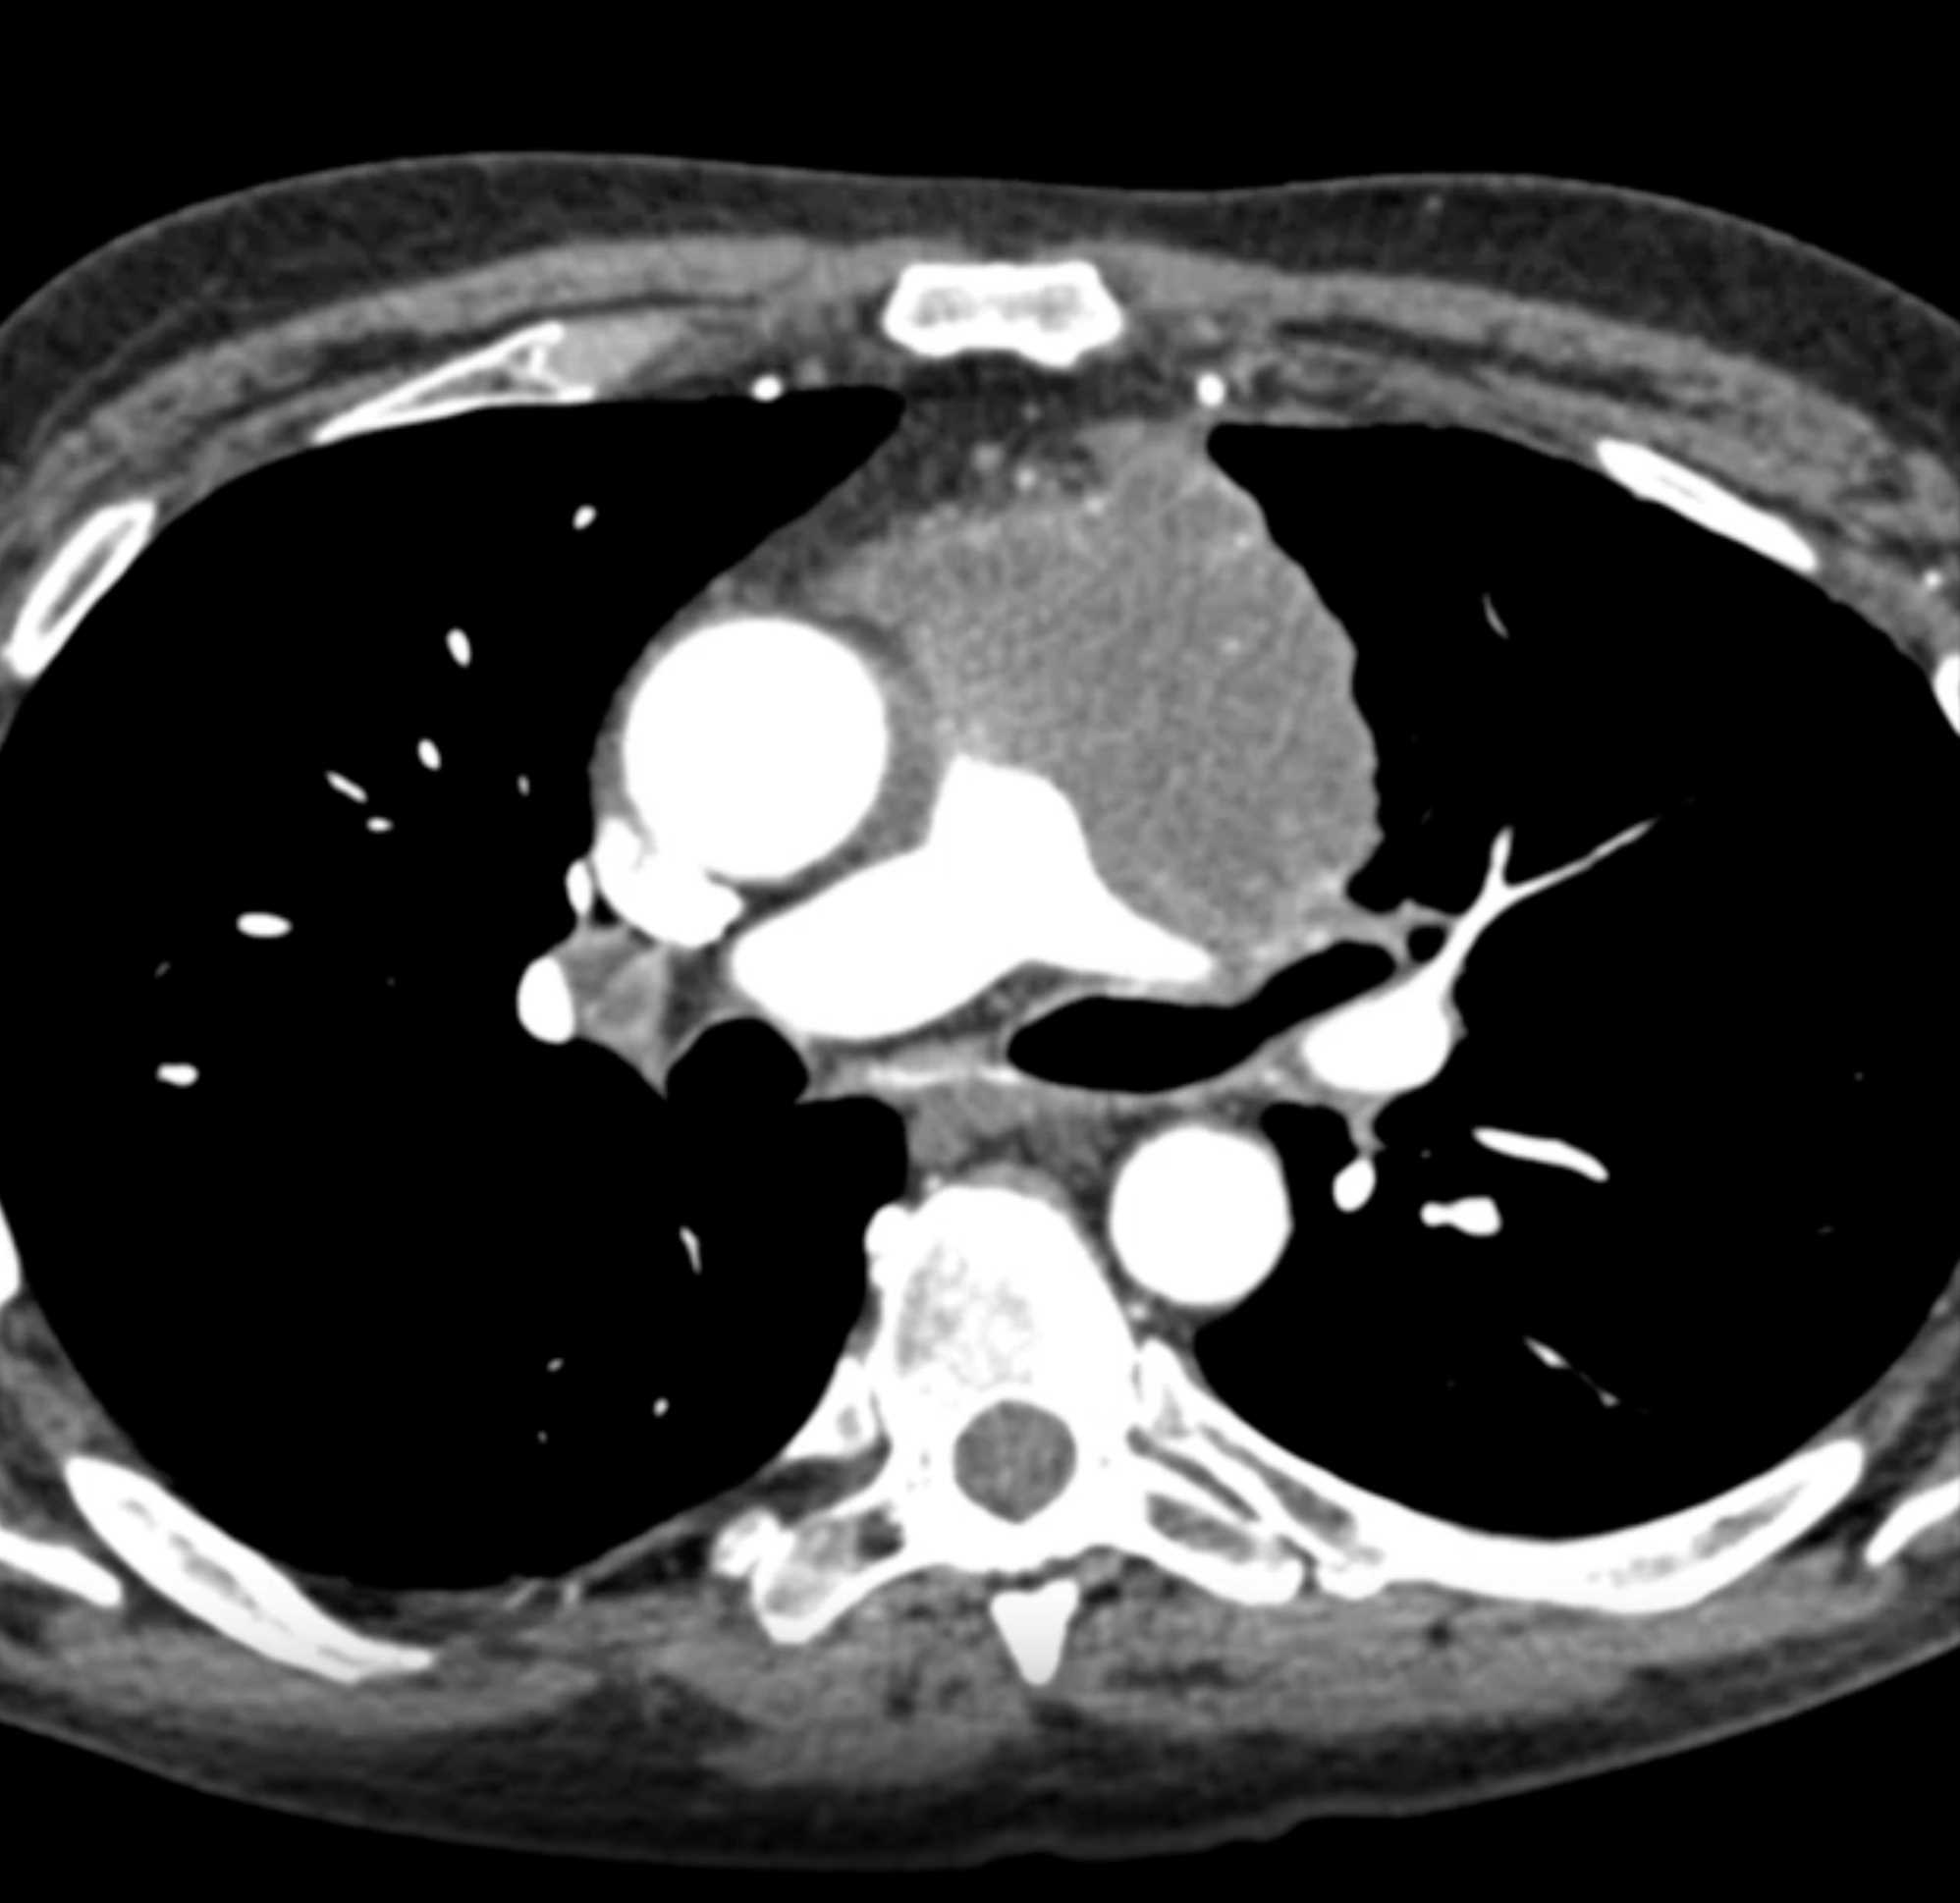

Thymic Carcinoma